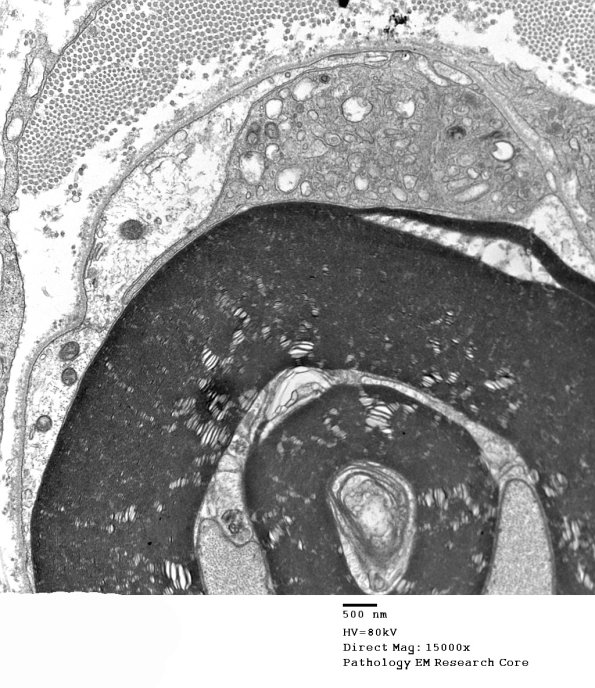

In this case it appears that the myelin stripping involves a Schmidt-Lanterman cleft. (electron micrographs)